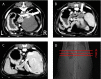

Fig. 4

Portography and three-dimensional computed tomography (3D-CT) images of a two-year-old female Shih tzu dog. (A): Portography after temporary occlusion in the remaining liver. Portal veins of the right medial hepatic lobe (large black arrow), right lateral hepatic lobe (white arrowhead) and caudate process of the caudate lobe (white arrow) were visualized, but no other vessels were observed. Large white arrow shows a gastroduodenal vein. (B): Preoperative 3D-CT image. Preoperative liver volume was 127 cc (18.4 cc/kg). Yellow: abnormal shunt vessel, red: artery, blue: vena cava and purple: portal vein. (C): Postoperative 3D-CT image. Postoperative liver volume was 187 cc (27.1 cc/kg). Gastroduodenal vessels were moved to left after surgery due to liver volume increasing.